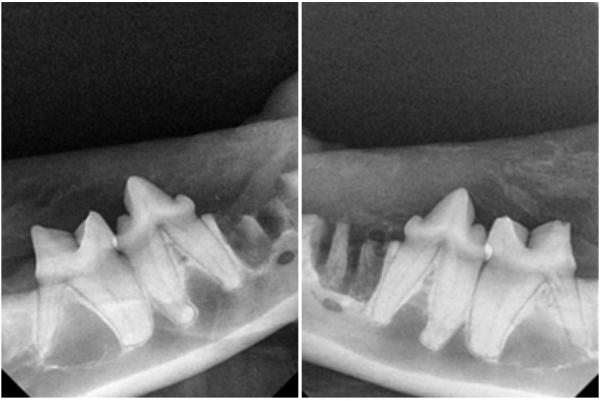

저희 이승진동물병원에서는,

발치 후에도 꼭 치과 방사선을 다시 촬영합니다.

남아 있는 뿌리가 없는지 확인하기 위함인데요.

미발치 된 뿌리가 있을 경우

또다시 통증을 유발할 수 있습니다.

울산 고양이치과 이승진동물병원에서는

치과 방사선 사진, 발치 부위, 최종 치아 상태를

리포트로 정리해 보호자님께 발송해드리고 있습니다.

사진과 설명이 함께 정리된 리포트를 통해

치료 경과를 쉽게 이해하시고,

이후의 관리도 정확하게 해주실 수 있습니다.